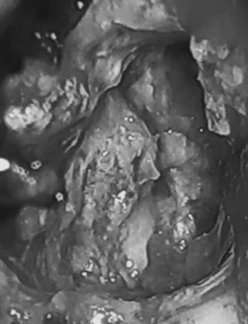

在开颅手术进行时,医生在Karanam大脑中发现了一个畸胎瘤,也就是我们上文提到的那个同卵双胞胎。这个畸胎瘤已经长出了骨头,头发和牙齿。

若提及那个畸胎瘤,Karanam总会开玩笑的称呼它为“邪恶双胞胎”。“我都不敢相信,它让我足足遭受了26年的痛苦。”Karanam说。